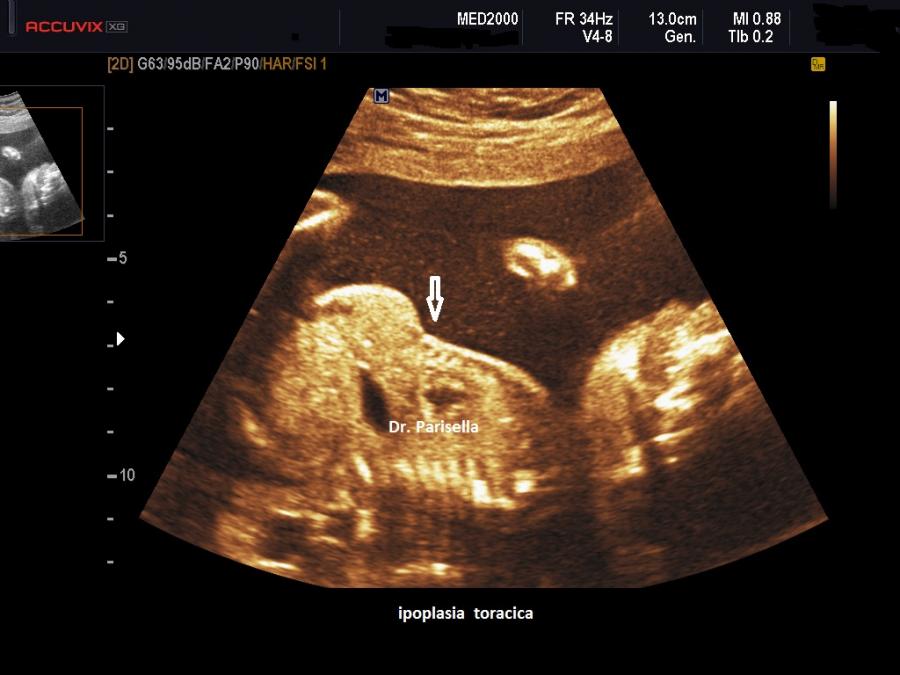

E' una displasia scheletrica caratterizzata da nanismo rizomelico con incurvamento del femore e della tibia. Si associano dismorfismo facciale (con micrognazia e palatoschisi), ipoplasia toracica  con coste corte (di solito sono presenti 11 paia di coste), ambiguità dei genitali fino al sex reversal (cariotipo maschile con fenotipo femminile); frequente è l'ipoplasia della fibula; si evidenzia inoltre piede torto, idrocefalia, macrocefalia.